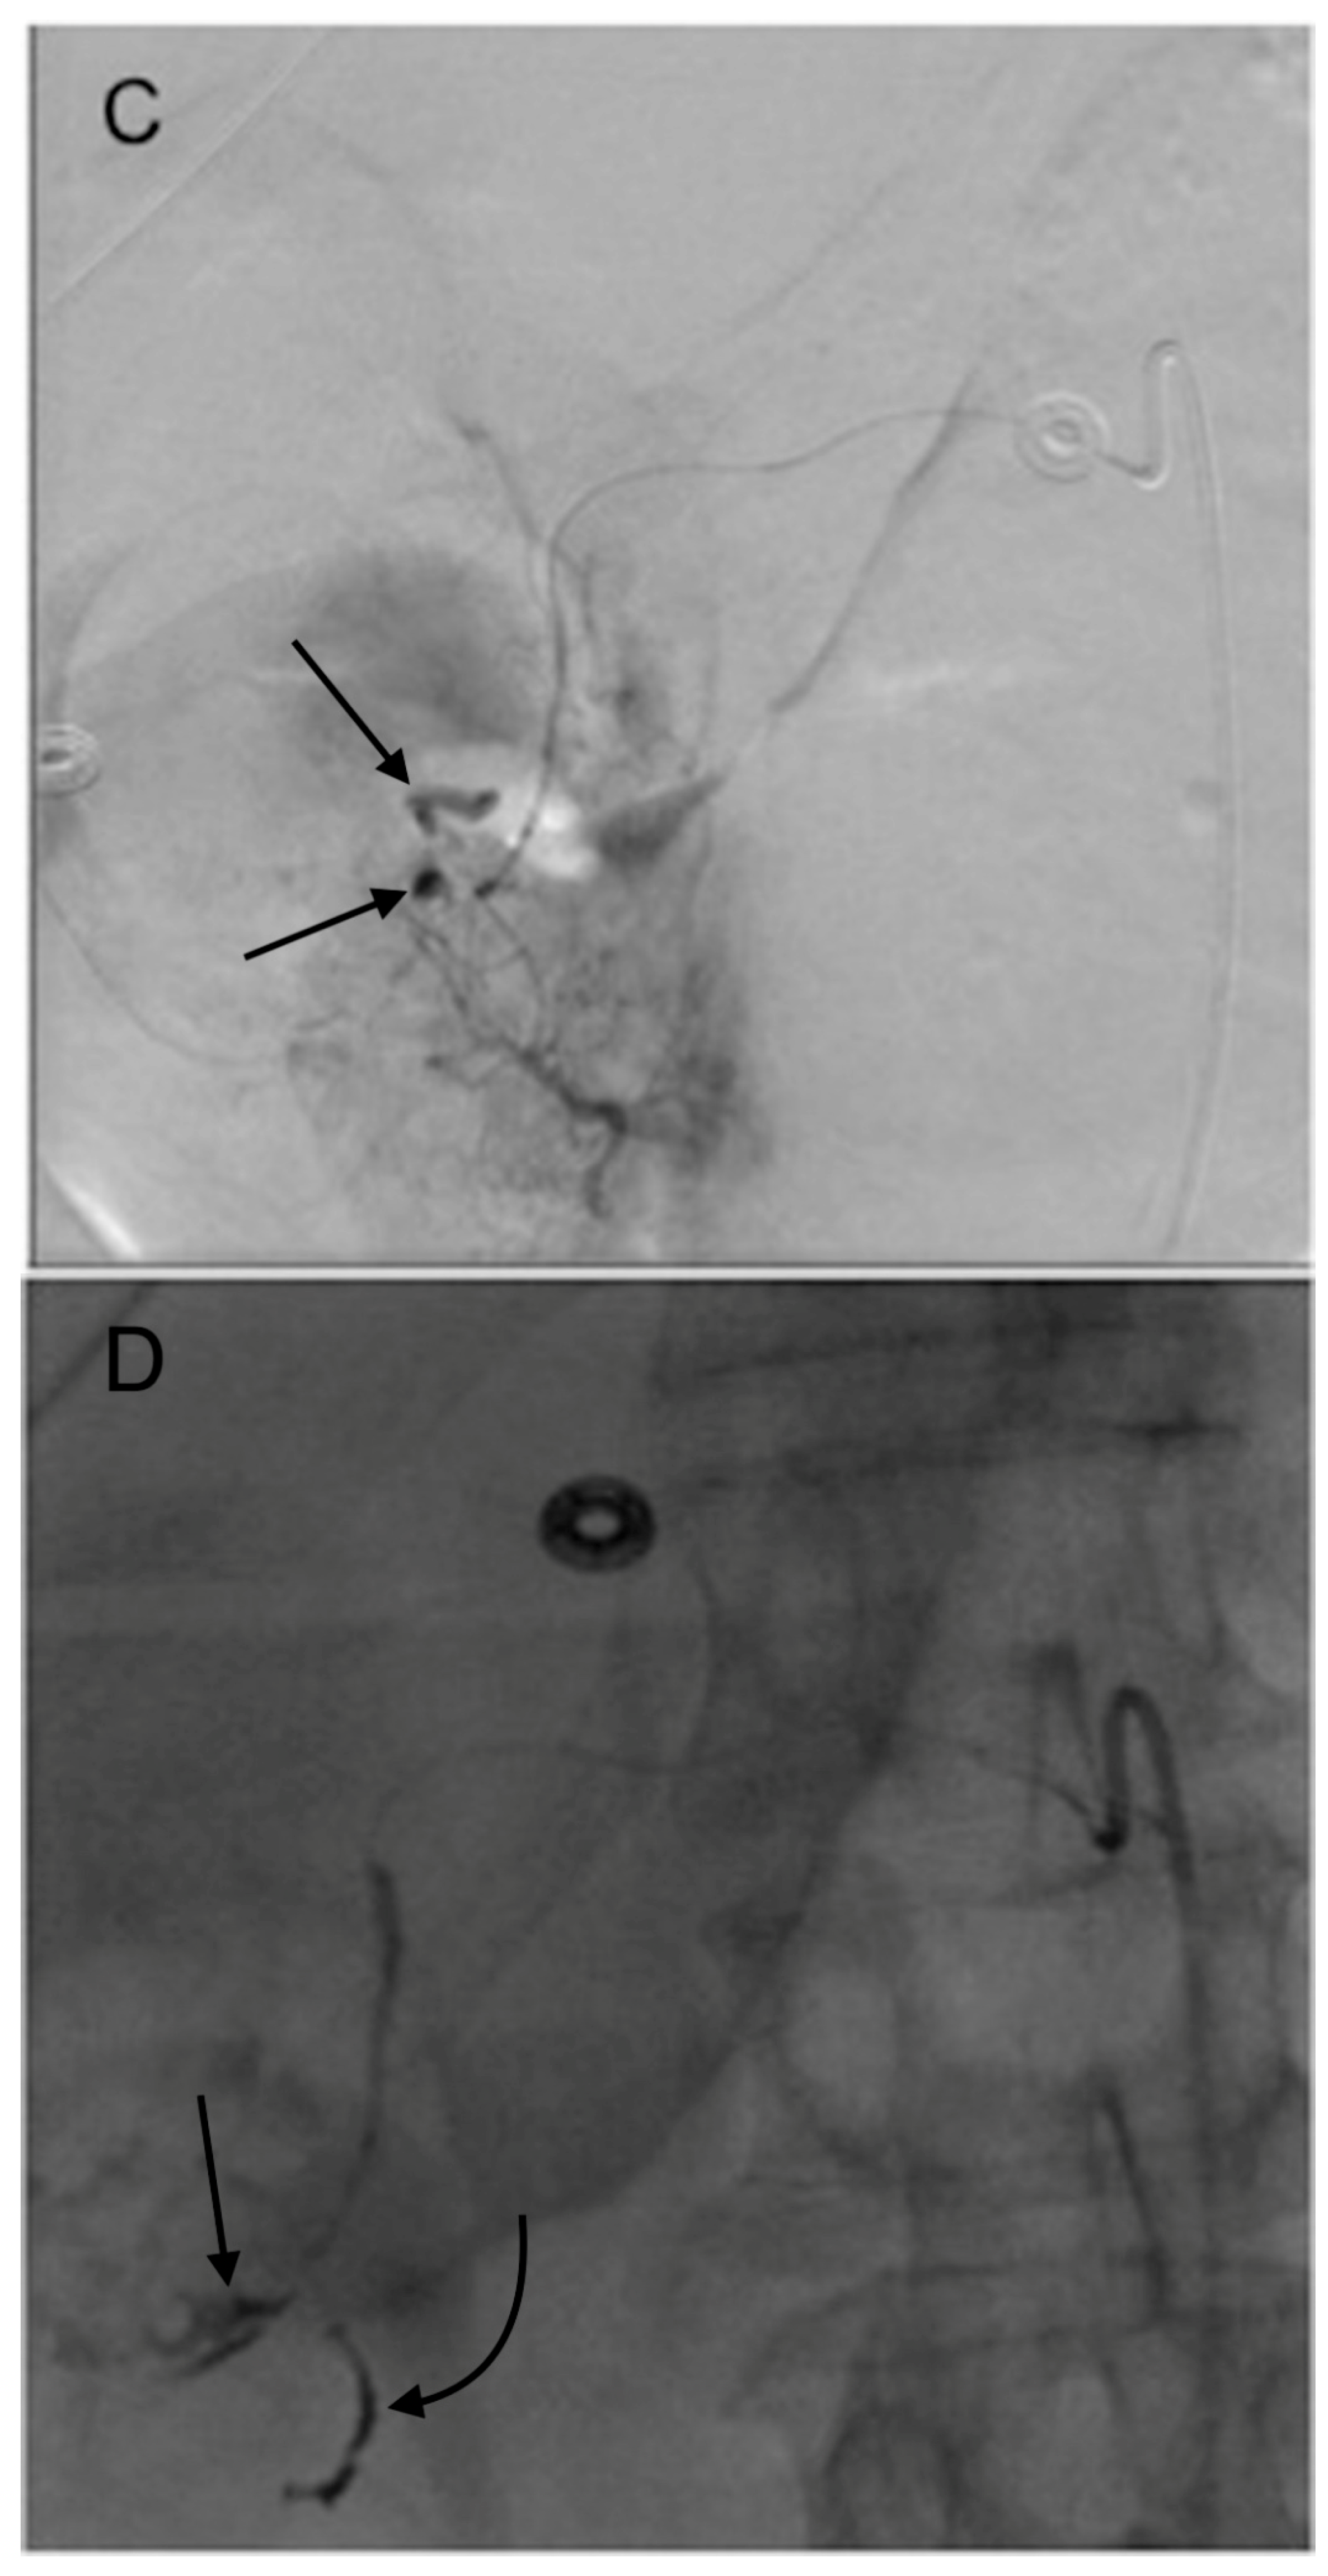

5. Pre-Y-90 GDA Embolization

- Lewandowski, R.J.; Sato, K.T.; Atassi, B.; Ryu, R.K.; Nemcek, A.A., Jr.; Kulik, L.; Geschwind, J.-F.; Murthy, R.; Rilling, W.; Liu, D. Radioembolization with 90Y microspheres: Angiographic and technical considerations. Cardiovasc. Interv. Radiol. 2007, 30, 571–592. [Google Scholar] [CrossRef] [PubMed]

- Schelhorn, J.; Theysohn, J.; Ertle, J.; Schlaak, J.; Mueller, S.; Bockisch, A.; Lauenstein, T. Selective internal radiation therapy of hepatic tumours: Is coiling of the gastroduodenal artery always beneficial? Clin. Radiol. 2014, 69, e216–e222. [Google Scholar] [CrossRef] [PubMed]

- Petroziello, M.F.; McCann, J.W.; Gonsalves, C.F.; Eschelman, D.J.; Anne, P.R.; Sato, T.; Doyle, L.A.; Frangos, A.; Brown, D.B. Side-branch embolization before 90Y radioembolization: Rate of recanalization and new collateral development. Am. J. Roentgenol. 2011, 197, W169–W174. [Google Scholar] [CrossRef] [PubMed]

- Enriquez, J.; Javadi, S.; Murthy, R.; Ensor, J., Jr.; Mahvash, A.; Abdelsalam, M.E.; Madoff, D.C.; Wallace, M.J.; Avritscher, R. Gastroduodenal artery recanalization after transcatheter fibered coil embolization for prevention of hepaticoenteric flow: Incidence and predisposing technical factors in 142 patients. Acta Radiol. 2013, 54, 790–794. [Google Scholar] [CrossRef] [PubMed]